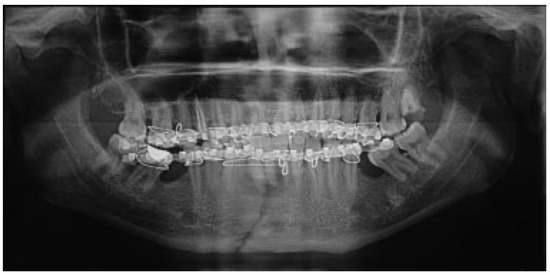

The mean for ramal height shortening was found to be 11.9 (0.99) preoperatively and 11.6 (1.57) postoperatively in Group A. It was compared using paired t-test and this difference was found not to be statistically significant (p = 0.34; Figure 1 and Figure 2). The mean for ramal height shortening was found to be 12.5 (0.84) preoperatively and (0.87) postoperatively in Group B. It was compared using paired t-test and this difference was found to be statistically significant (p < 0.05; Figure 3 and Figure 4).

Figure 2.

Group A: Postoperative orthopantomography.